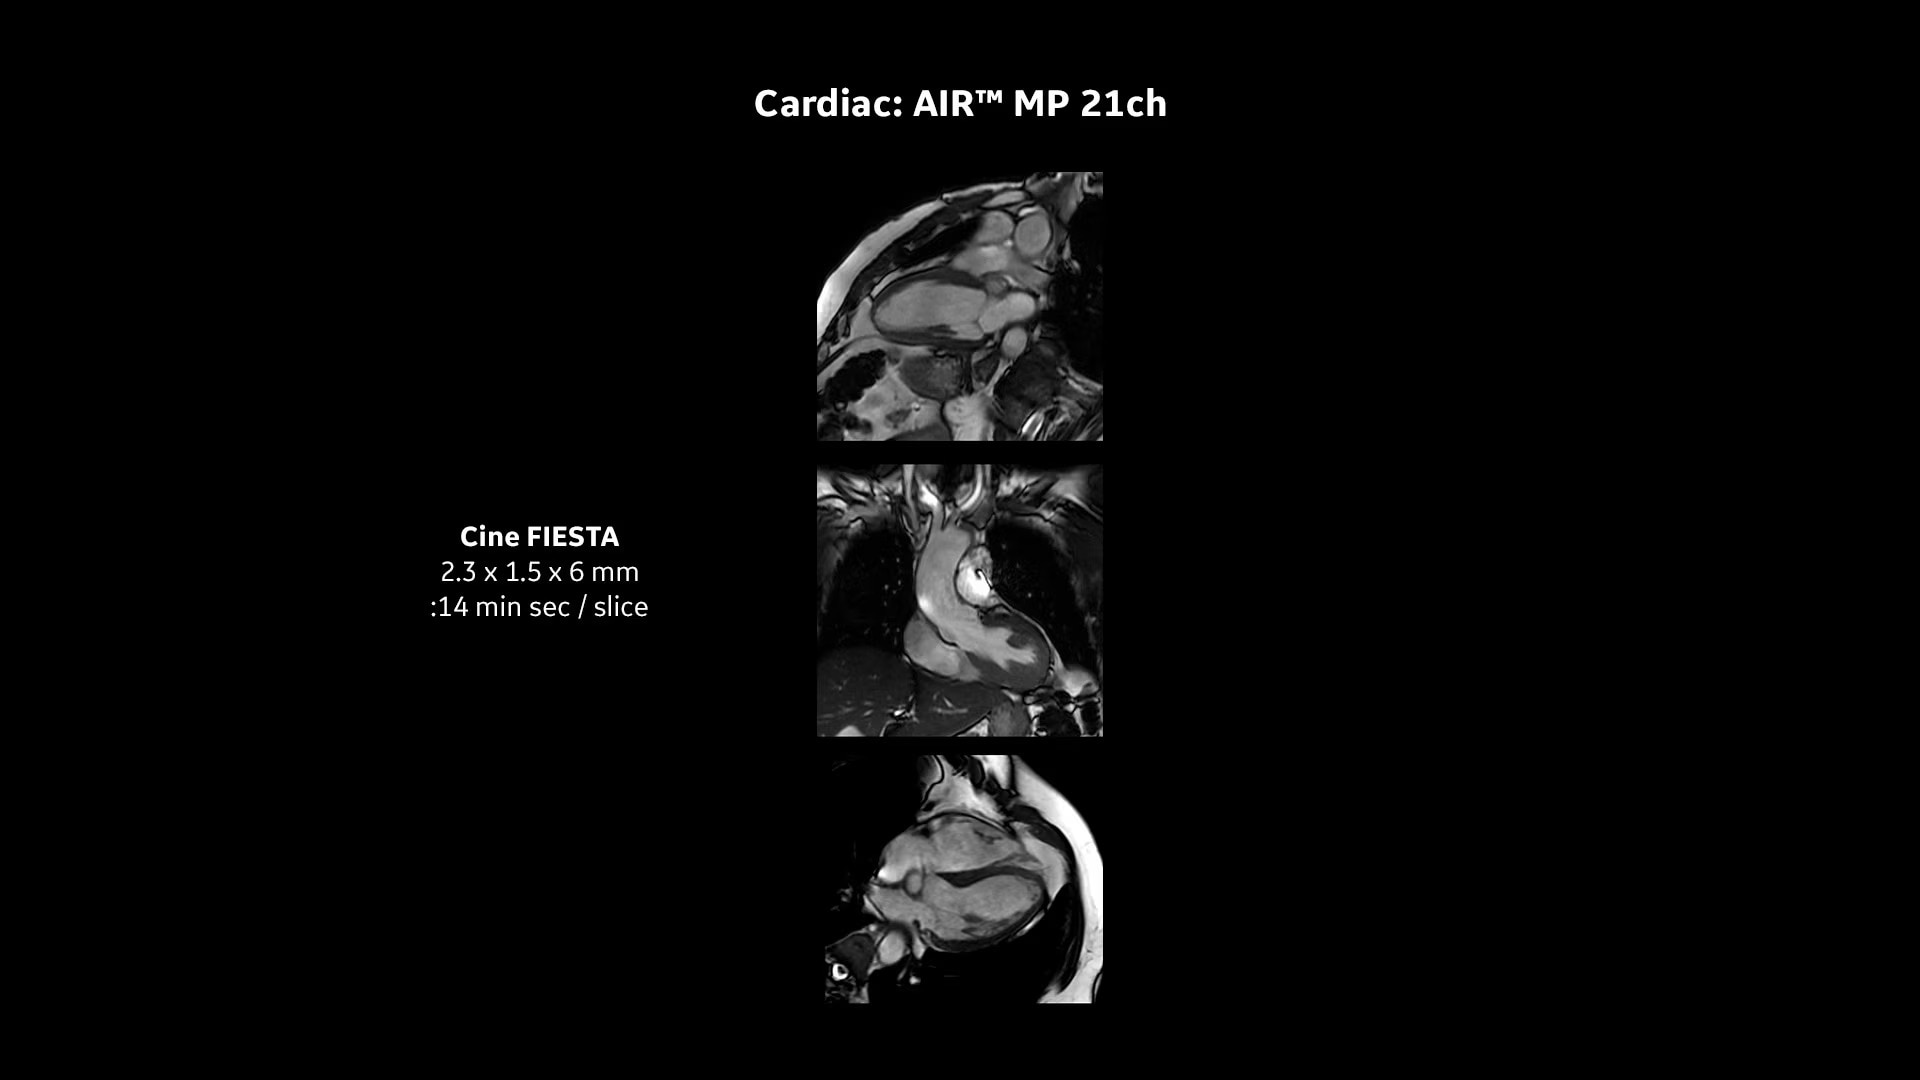

AI-Enhanced cardiac MR

Perform quantification and mapping with revolutionary deep learning

Capture clarity

Improve SNR and image sharpness by up to 60% with AIR™ Recon DL